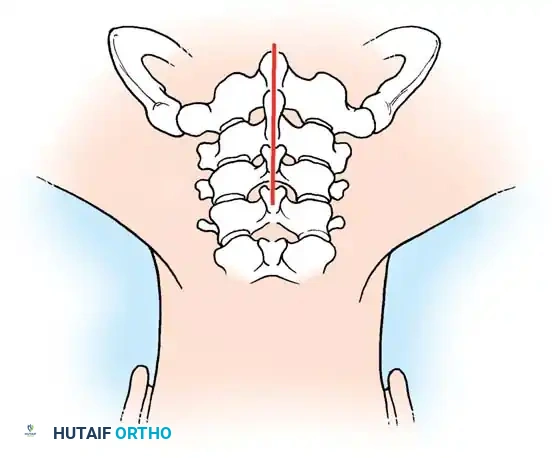

Step 1: Posterior Exposure

The patient is positioned prone, often using a Mayfield head holder. A midline posterior incision is made, and the paraspinal musculature is subperiosteally elevated off the spinous processes and laminae on the symptomatic side.